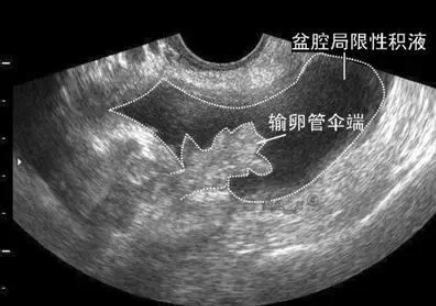

盆腔積液就是盆腔存在炎性滲出物,可發生在子宮內膜發炎后,內膜組織腫脹的細胞中滲出的略黏稠的液體,被周圍組織包裹所漸漸形成的囊性包塊。如果不加以治療的話,會慢慢長大。太大了,藥物就不能消除了,需要手術切掉。盆腔積液可以徹底治愈,但必須在查清致病菌的基礎上,才能夠有效治療。

5、手術治療:對于異位妊娠、黃體破裂出血較多的情況,應該及時進行手術治療。同時如果存在腫塊、輸卵管積水或者是輸卵管卵巢囊腫的情況下也可進行手術治療;對于年輕婦女來說應盡量保留其卵巢的功能。而對于慢性盆腔炎來說僅僅使用單一療法的話效果較差,如果改用綜合治療效果更佳。